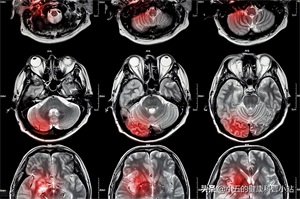

医生通过检查颅脑磁共振和血管造影后,诊断孙奶奶是患上了血管性痴呆,并且给孙奶奶开具了几种药物,其中一种药物叫奥拉西坦